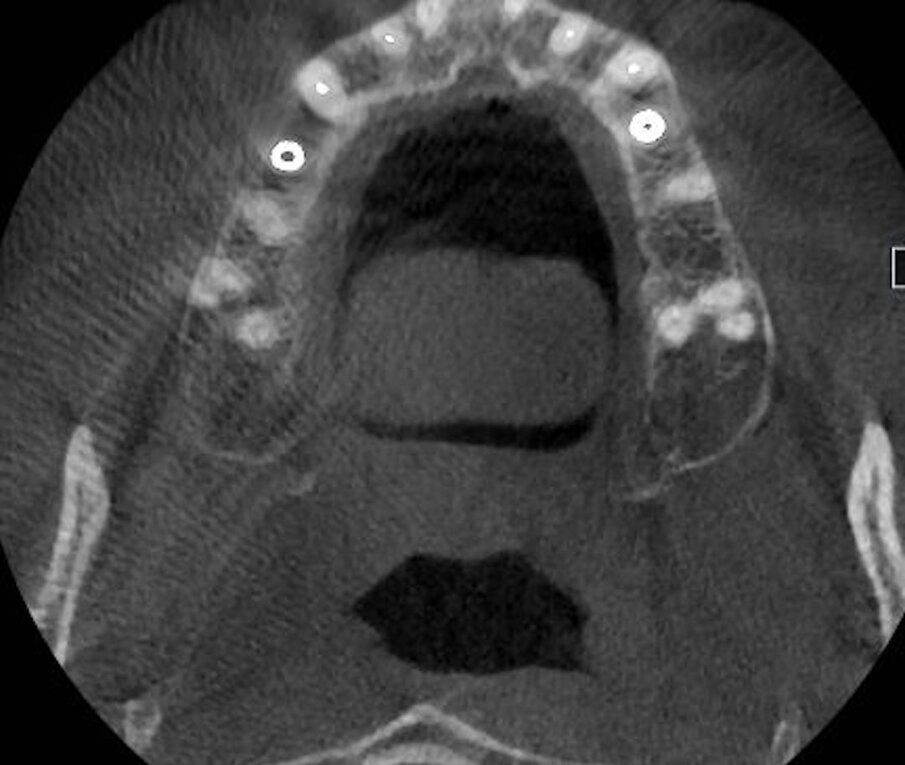

La cone beam rivela il mantenimento volumetrico del tessuto osseo periimplantare (Figg. 6a-6c). Questo case report evidenzia l’importanza della customizzazione delle cappette di guarigione per il mantenimento dei volumi dei tessuti perimplantari. La forma delle cappette di guarigione simili alle radici dei denti estratti avvitate sugli impianti post-estrattivi evitano il collasso volumetrico dei tessuti, guidando la guarigione dei tessuti perimplantari con il mantenenimento volumetrico dell’alveolo. Con questa metodica si riduce il numero delle procedure tradizionali eseguite per il trattamento implanto protesico negli impianti post-estrattivi. Si evita la riapertura del lembo gengivale, le varie fasi della ribasatura del provvisorio per il condizionamento gengivale, riducendo i tempi e i costi. Con questa procedura si lavora in modo conservativo, si velocizzano i tempi di esecuzione del flusso di lavoro mantenendo inalterati i parametri morfologici e volumetrici dei tessuti periimplantari. E tutto questo flusso di lavoro è possibile effettuarlo direttamente alla poltrona diminuendo i costi e il tempo per il paziente.

Fig. 1b - La sezione alla Cone beam.

Fig. 6b, 6c - Le sezioni alla Cone beam mostrano il mantenimento volumetrico dell’osso alveolare.